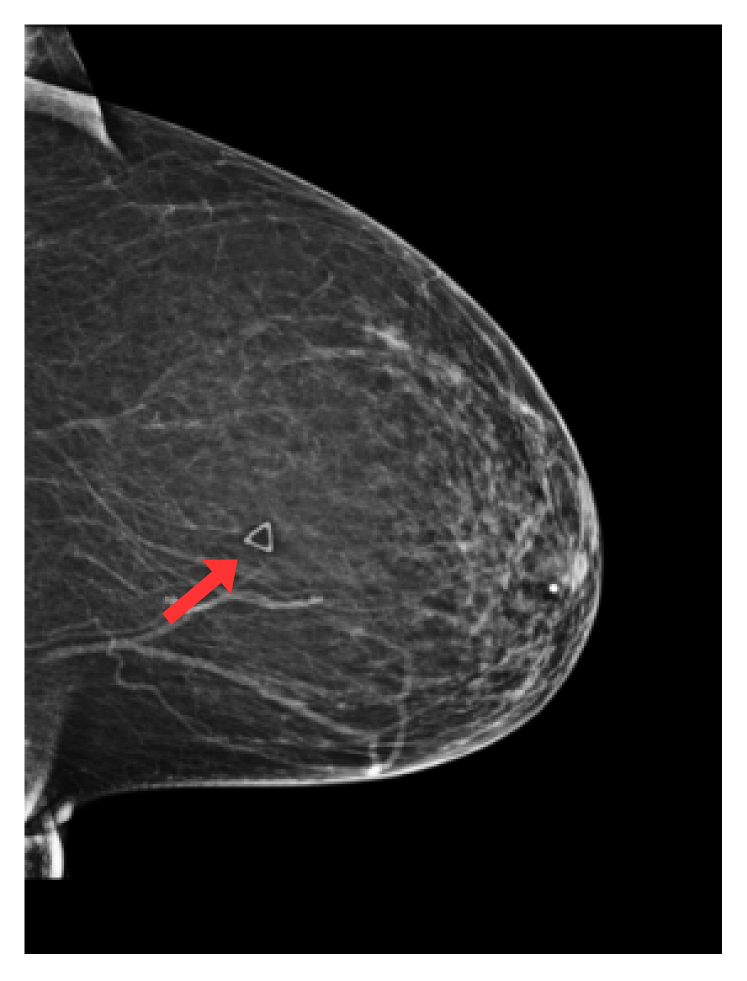

Refer to caption

(a) Circular marker

(b) Triangular marker

Fig. 1: Radio-opaque artefacts considered in this study: skin markers (circle and triangles), breast implants, support devices (e.g. pacemakers) and spot compression (or magnification) devices. Red arrows highlight artefacts of interest.

We focus on five types of artefacts: (a) circular skin markers, (b) triangular skin markers, (c) breast implants, (d) devices (e.g. pacemakers), (e) compression and special magnification artefacts. Examples of such artefacts can be found in Fig. 1. Circular and triangular skin markers are radio-opaque markers placed on the breast skin by radiologists at acquisition time [8], indicating locations of moles (circle) or a palpable mass (triangle). Breast implants and devices such as pacemakers or metallic sensors appear as large, very high contrast structures on the mammograms. Similarly, spot compression and special magnification devices are large radio-opaque structures surrounding the breast area, allowing magnification of small, suspicious regions of breast tissue. Despite their clear effect on image appearances, the effect of the presence of such artefacts in mammograms on downstream task models (e.g. breast cancer screening) has - to the best of our knowledge - not been studied so far. This is largely explained by the fact that labels indicating the presence of such artefacts within an image are not typically available in current publicly available mammography datasets.